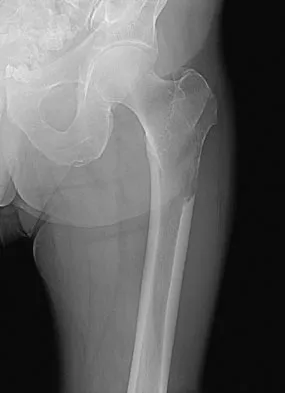

Figure 7 shows the AP radiograph of a 60-year-old man who has had pain in the thigh for past 6 months. History reveals that he underwent hip replacement 1 year ago. The radiographic changes are most likely the result of what process?

Explanation

The arrows in the radiograph point to circumferential radiolucencies that strongly support the diagnosis of septic loosening. Radiolucent lines that occur in such a short time are also typical of an infection. Garvin KL, Hanssen AD: Infection after total hip arthroplasty: Past, present, and future. J Bone Joint Surg Am 1995;77:1576-1588.